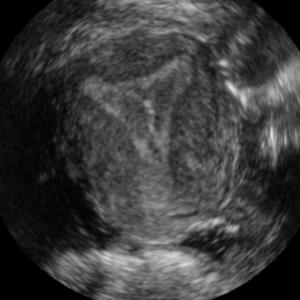

Standard plane (SP) localization is essential in routine clinical ultrasound (US) diagnosis. Compared to 2D US, 3D US can acquire multiple view planes in one scan and provide complete anatomy with the addition of coronal plane. However, manually navigating SPs in 3D US is laborious and biased due to the orientation variability and huge search space. In this study, we introduce a novel reinforcement learning (RL) framework for automatic SP localization in 3D US. Our contribution is three-fold. First, we formulate SP localization in 3D US as a tangent-point-based problem in RL to restructure the action space and significantly reduce the search space. Second, we design an auxiliary task learning strategy to enhance the model's ability to recognize subtle differences crossing Non-SPs and SPs in plane search. Finally, we propose a spatial-anatomical reward to effectively guide learning trajectories by exploiting spatial and anatomical information simultaneously. We explore the efficacy of our approach on localizing four SPs on uterus and fetal brain datasets. The experiments indicate that our approach achieves a high localization accuracy as well as robust performance.